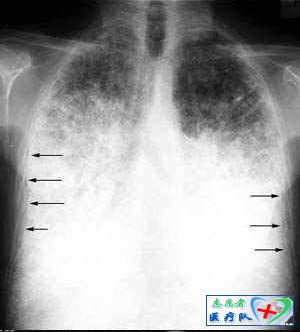

10、横S征(反S征):

当肿瘤发生于右上叶支气管时,X线可见右肺门肿块与右上叶不张相连,构成形似S横着写的征象,为右上叶中央型肺癌特征性表现。因为右肺上叶位于斜裂前方,下方以水平裂为界,侧方位胸壁,内测是纵隔。当右肺上叶容积缩小,根据容积缩小的程度出现的解剖改变包括胸膜裂移位、结构变化及肺密度增加。在右肺上叶不张时水平裂和斜裂向纵隔方向向上、内移动,右肺中、下叶代偿性膨胀,后前位胸部X线片上可见水平裂向下凹,形成代表肺叶不张三角形密度影,尖端指向肺门,外缘以胸壁为宽基,严重的右上肺不张可以与纵隔平行,和纵隔宽相似,或向上压缩如尖帽。此时,如果有一个较大的肺门肿块出现,与凹面向下的水平裂结合,在后前位胸部平片上就形成横S征。其实,不只是在右肺上叶,只要肿瘤或淋巴结压迫上叶支气管导致肺不张,就会由肿块和不张肺边缘形成此种征象。其次,横S征也不是只在X线上看到,在CT上同样可以见到。上一篇:浅谈女性的生理周期 下一篇:膝关节疼痛的诊断与鉴别诊断